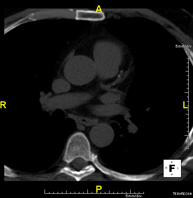

- TC Tórax

Prueba diagnóstica que consiste en obtener imágenes del tórax de alta definición anatómica (pulmones, corazón, mediastino, grandes vasos, caja torácica, etc.) mediante el empleo de un equipo de TC (Tomografía Computarizada). Dichas imágenes se estudian posteriormente en una estación de trabajo que permite reconstrucciones bidimendionales en diferentes planos del espacio y también reconstrucciones 3D (volumétricas). Algunos estudios requieren el empleo de contraste yodado para mejorar la definición de las imágenes. - Angio-TC Aorta torácica